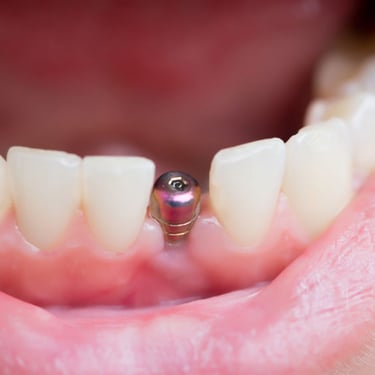

Pérdida de un diente único

La pérdida de un diente único es cuando un solo diente se ha caído o ha sido extraído, y se necesita un implante para reemplazarlo.

Los pacientes pueden notar un espacio donde solía estar el diente. Esta condición puede afectar la estética y la función masticatoria.

El tratamiento incluye la colocación de un implante dental para restaurar el diente perdido.